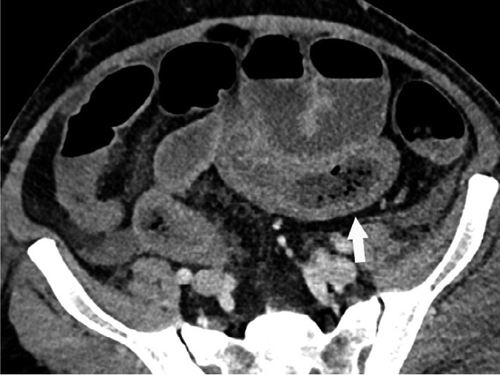

这项研究包括了412名新型冠状病毒检测阳性的患者的数据,研究人员发现,在17%的患者在治疗过程中接受腹部造影检查的患者中,近三分之一的CT扫描显示肠道异常。

“我们在COVID-19患者的影像学上发现了肠道异常,更常见的是那些去ICU的病人,”马萨诸塞州总医院的Rajesh Bhayana博士在一份声明中说。“一些研究结果是典型的缺血性肠病或肠坏死。在那些做了手术的患者中,我们看到肠坏死部位旁边的小血管凝块。ICU中的患者可能因为其他原因导致肠缺血,但我们知道COVID-19会导致凝血和小血管损伤,所以肠道可能也会受到影响。”